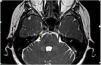

Materials and methodsFifty-three patients with typical TGN underwent GKRS from May 2012 until December 2022. Among these patients, 45 patients who were follow-up for at least 12 months were included in the study. A mean dose of 87.5 Gy (range, 80–90) was administered to the trigeminal nerve. Postoperatively, outcome was considered excellent if the patient was pain- and medication-free.